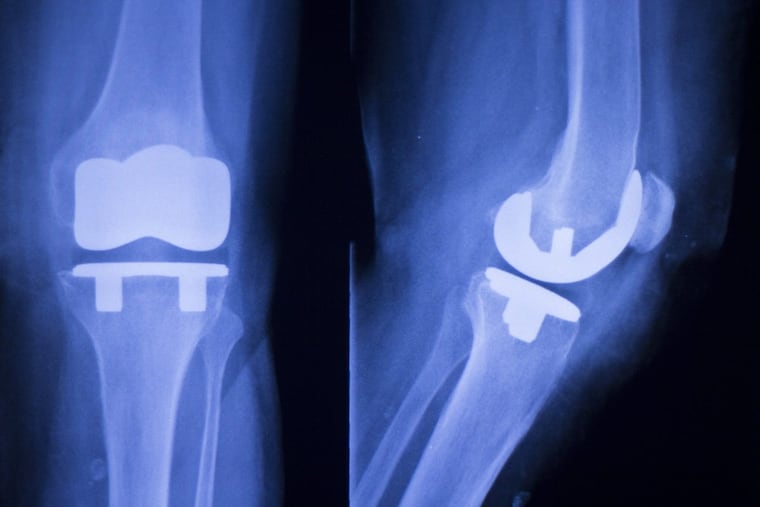

Every year, more than 700,000 Americans undergo knee replacement surgery. And researchers expect the procedure will only become more common as people strive for an active, pain-free life as they age.

People usually get a total knee replacement when they’re no longer able to move through their daily life without constant pain. But, how can you build healthy, strong knees today that power you through walks and workouts for decades?